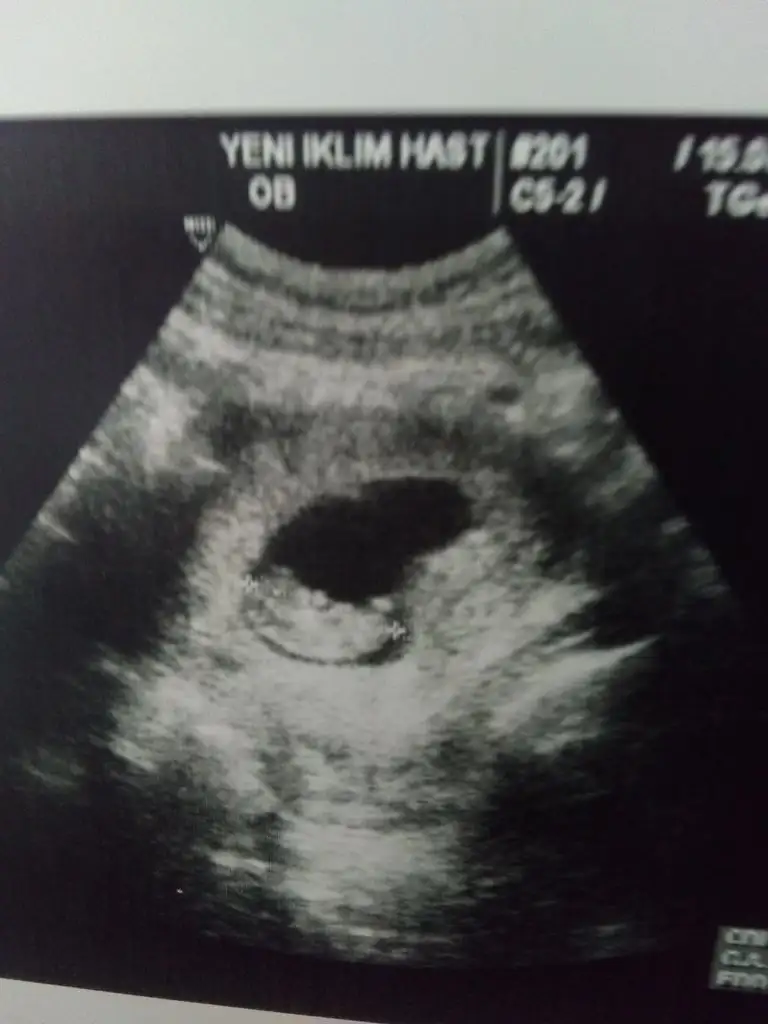

9+0 olmamız gerek ama ultrasonda 9+6 çıktık :) cinsiyet tahmini nedir? :)))